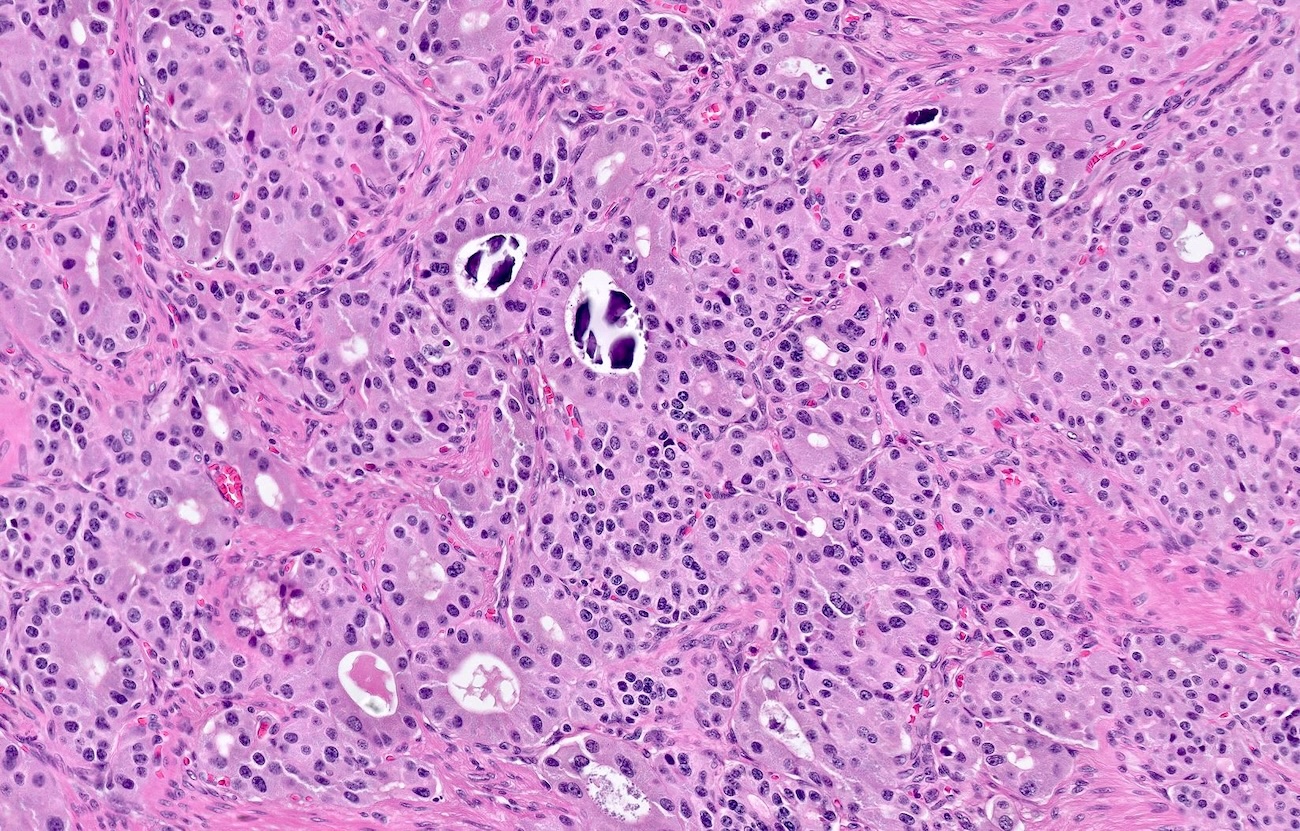

- Pancreatic neuroendocrine tumors

- Well differentiated NETs composed of uniform polygonal cells with eosinophilic or clear cytoplasm, salt and pepper chromatin (finely granular nuclear chromatin) (Arch Pathol Lab Med 2025 Mar 4 [Epub ahead of print])

- Some tumors may show vascular invasion or mitotic activity, indicating more aggressive potential

- Diffuse islet cell hyperplasia occurs frequently (World J Gastroenterol 2011;17:137)

- Multiple pancreatic microadenomas or microtumors are a common feature of MEN1 associated PanNETs and serve as a useful clue to the diagnosis of MEN1